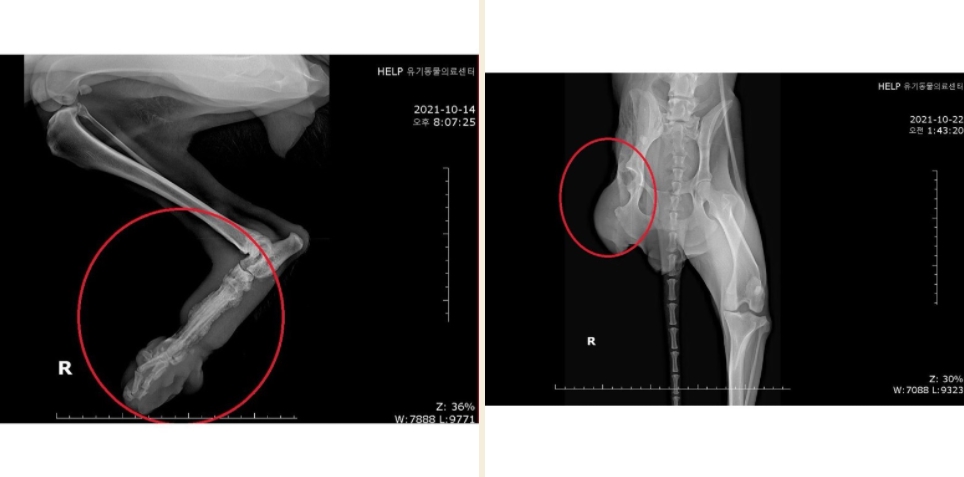

¾È³ç Çüµé! ¿À´Ã ¼Ò°³ÇÒ ¾ÆÀÌ´Â µ£¿¡ °É·Á º´¿ø¿¡ ¿À°Ô µÈ ´ó´óÀ̸¦ ¼Ò°³Çغ¸·Á°í ÇØ. À̸§Àº ¾ÆÅ°ÄÚ! »óŰ¡ ½É°¢Çؼ ±¸Á¶ Ä¡·á°¡ Àý½ÇÇÑ »óȲÀ̾ú¾î. £¨º¸È£¼Ò¿¡¼ ¸· µµÂøÇßÀ» ¶§ »çÁøÀÓ£© Áö³ 10¿ù 14ÀÏ, ±¸Á¶µÇ¾î ¿ì¸® º´¿øÀ¸·Î ¿Ô°í, ´ç½Ã ¹ß°¡¶ô »À°¡ ¸¹ÀÌ ³ì¾ÆÀÖ¾ú°í, °ñ¼ö¿°µµ ¸Å¿ì ½ÉÇÑ »óÅ¿´¾î. £¨ »À°¡ ´Ù º¸ÀÏ Á¤µµ ¤Ð¤Ð£© Å»¼ö¿Í ¿µ¾ç½ÇÁ¶µµ ¸Å¿ì ½ÉÇß°í, ½ÉÀå»ç»óÃæµµ °¨¿°µÇ¾îÀÖ¾ú°í, üÁßµµ ³Ê¹« Àû°Ô ³ª°¬¾î..¤Ð ¤Ð Åп¡ º¯/¼Òº¯ ¶§¹®ÀÎÁö ³¿»õ°¡ ½ÉÇØ¼ ¸ñ¿åµµ 3¹ø Çß³ß! ±×·¡µµ °£/½ÅÀå µî Àå±â ¹× Àü¹ÝÀûÀÎ °Ç°»óÅ´ ±¦Âú¾Ò¾î. º´¿ø¿¡ ¿Â ´çÀÏ ¾à+ĵ+»ç·á ÇÏÆ® ºñºö¹äÀ» ¸¸µé¾îÁÖ¾ú´Âµ¥, ¿ÏÀü Çã°ÌÁö°Ì ¸Ô´õ¶ó ¤Ð¤Ð ¤Ð¤Ð¤Ð ¤Ð ¿ÏÀü ¼ø»è ¤§¤§ ÀÌ·¸°Ô º´¿ø¿¡¼ ¾à 1ÁÖÀϰ£ ¼ö¾× ¹× ¿µ¾çº¸Ãæ Çß¾î. £¨¾ÆÅ°ÄÚ ÁøÂ¥ ÁøÂ¥·ç ¾äÀüÇϰí ÂøÇØ ¤Ð¤Ð£© ±×¸®°í Áö³ 10¿ù 22ÀÏ, ¿ìÃø µÞ´Ù¸® ÀûÃâ ¼ö¼úÀ» ¹Þ¾Ò¾î. °í°üÀýºÎÅÍ ´Ù¸® Àüü¸¦ ¸öÅë¿¡¼ ºÐ¸®ÇÏ¿© ¶¼¾î³Â¾î. Å« ¼ö¼úÀ̾ú´Âµ¥ ¾ÆÅ°ÄÚµµ Àß ¹öÅßÁÖ¾ú°í, ¾ÆÇà ÅÙµ¥ ¹äµµ Àß ¸Ô¾îÁ༠¾ó¸¶³ª »ÑµíÇÏ°í °í¸¶¿ü´ÂÁö ¸ô¶ó. µÞ´Ù¸® ÀýÁ¦¼úÀÇ ¸î ¾ÈµÇ´Â ¼úÈÄ ¹ß»ýÇÏ´Â ¹®Á¦ Áß Çϳª°¡, ¼ö¼ú ºÎÀ§¿¡ ¿°ÁõÀ̳ª ¾×ü°¡ Â÷´Â °ÍÀε¥ ±×·± °Í ¾øÀÌ Á¤¸» Àß È¸º¹Çß¾î!! ³Ê¹« ¸¶¸£°í ±ÙÀ°ÀÌ ¸¹ÀÌ À§ÃàµÇ¾îÀÖ¾î¼ °ÆÁ¤Çߴµ¥, ´ÙÇàÈ÷ Àß À̰ܳ»ÁÖ¾ú¾î. £¨Àß °È°í, Àß ¶Ù¾î!£© ¾î´ÀÁ¤µµ ȸº¹ÇÑ ¾ÆÅ°ÄÚ´Â ¿ù¿äÀÏÀÎ ±×Àú²² ÀÓº¸Ã³·Î À̵¿Çߴµ¥, ³Ê¹«³Ê¹« ±Í¿±Áö ¾Ê¾Æ? ¾ÆÅ°ÄÚ´Â ¹Ì±¹ ÅØ»ç½º·Î ÇØ¿Ü ÀÔ¾ç °¥ ¿¹Á¤À̶ó°í ÇØ! ³Ñ³Ñ Àß µÆÁö ¤Ð¤Ð¤Ð ÇÏÁö¸¸ ÅØ»ç½º·Î °¡´Â ÇØ¿ÜÀ̵¿ºÀ»çÀÚ´Â ¾ÆÁ÷ ¸ø ±¸Çß´Ù°í Çϴµ¥... Ȥ½Ã ³»³â 1¿ù ¹Ì±¹À¸·Î °¡´Â Çü ÀÖÀ¸¸é ÂÊÁö ºÎÅ¹ÇØ!! ¾ÆÅ°ÄÚ ÀÌÁ¦ º¸È£¼Ò°¡ ¾Æ´Ñ, µû¶æÇÑ Áý¿¡ »ì°Ô µÇ¾î¼ ³Ê¹«³Ê¹« ´ÙÇàÀÌÁö ¤Ð¤Ð!! Å« ¼ö¼úµµ À̰ܳ»°í, °í»ý ¸¹¾Ò¾î! ±×·³ Á¶¸¸°£ ¶Ç º¸ÀÚ »ç¶ûÇØ ¤Ð¤Ð¤Ð